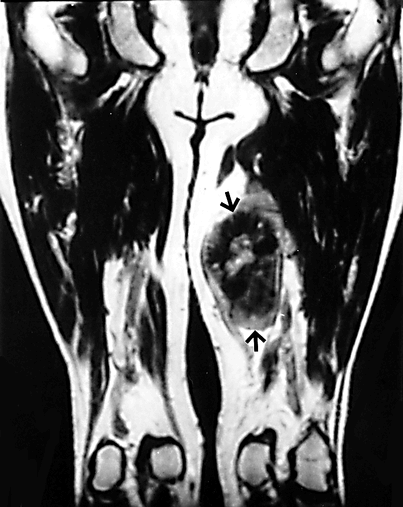

Онкология. Саркома. Экстраскелетная остеосаркома. +

Экстраскелетная остеосаркома мягких тканей - это высокозлокачественная редкая опухоль, составляющая, по данным разных авторов, 1-1,2% всех злокачественных сарком мягких тканей и 4% всех остеогенных сарком, чаще встречается у мужчин и в возрасте 50-60 лет. Ранними клиническими проявлениями являются боль и припухлость, причем чаще отмечается только припухлость. Сроки развития клинических симптомов до начала лечения составляют в среднем от 6 мес до 2 лет. Наиболее часто опухоль поражает нижние конечности - бедро в 47-70% случаев, в 20-23% - верхние конечности, в 7-17% случаев опухоль локализуется ретроперитонеально. Внескелетные остеогенные саркомы могут встречаться в печени, желчном пузыре, молочной железе. Наличие внескелетной остеогенной саркомы позволило предположить о возникновении данной опухоли из мультипотентных мезенхимальных клеток.

Прогноз заболевания остается плохим, чувствительность к химиотерапии очень низкая. Диагноз экстраскелетной остеосаркомы может быть установлен только после исключения наличия костных очагов опухоли.

Снимки из из архива AFIP